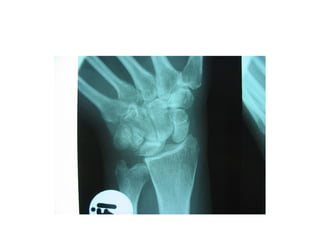

This document discusses several cases of scaphoid fractures in different patients. A 42-year-old female presented with carpal tunnel syndrome and wrist pain after a fall and was found to have a large cyst and fracture in her scaphoid bone. A 16-year-old male reported four months of painful wrist after a skateboarding injury. Imaging also showed a non-union in the wrists of a 42-year-old man bilaterally. Surgical treatment including open reduction and internal fixation with bone grafting was performed in some cases.